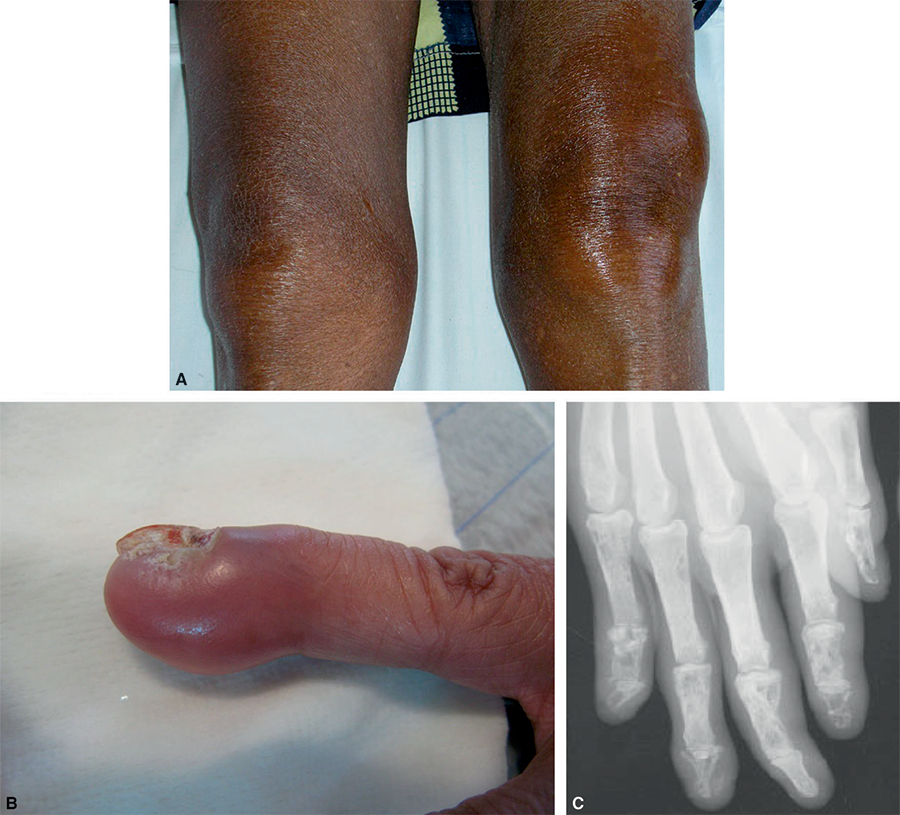

2.2 - Autres manifestations rhumatologiques (fig. 23.3)

Fig. 23.3. Sarcoïdose maladie : mono-, oligo- ou polyarthrites aiguës, arthropathies chroniques.

A.

Arthrite du genou gauche. B. Dactylite. C. Atteinte osseuse.

2.2.1 - Dactylite

L'atteinte de la main est la plus fréquente et est associée à une atteinte osseuse de la maladie.

Elle se présente sous forme d'une dactylite inflammatoire, uni- ou bilatérale, de la deuxième et troisième phalange, fréquemment asymptomatique ou peu douloureuse. Il peut exister une atteinte unguéale associée (onychodystrophie, hyperkératose sous-unguéale, décoloration, stries longitudinales, onycholyse).

2.2.2 - Atteinte osseuse

L'atteinte osseuse, souvent asymptomatique, est sous-diagnostiquée. L'atteinte osseuse est parfois associée à une atteinte de la peau et des tissus mous. L'ensemble du squelette peut être atteint. L'atteinte des mains est la plus fréquente, suivie par celle du crâne, des os de la face, du sternum, des côtes, des vertèbres et des os longs.

Sur les radiographies des mains, on peut trouver soit un kyste circonscrit (ostéite cystoïde), soit de multiples lacunes de petite taille réalisant souvent un aspect grillagé. Plus rarement, un aspect d'acro-ostéolyse peut être détecté.